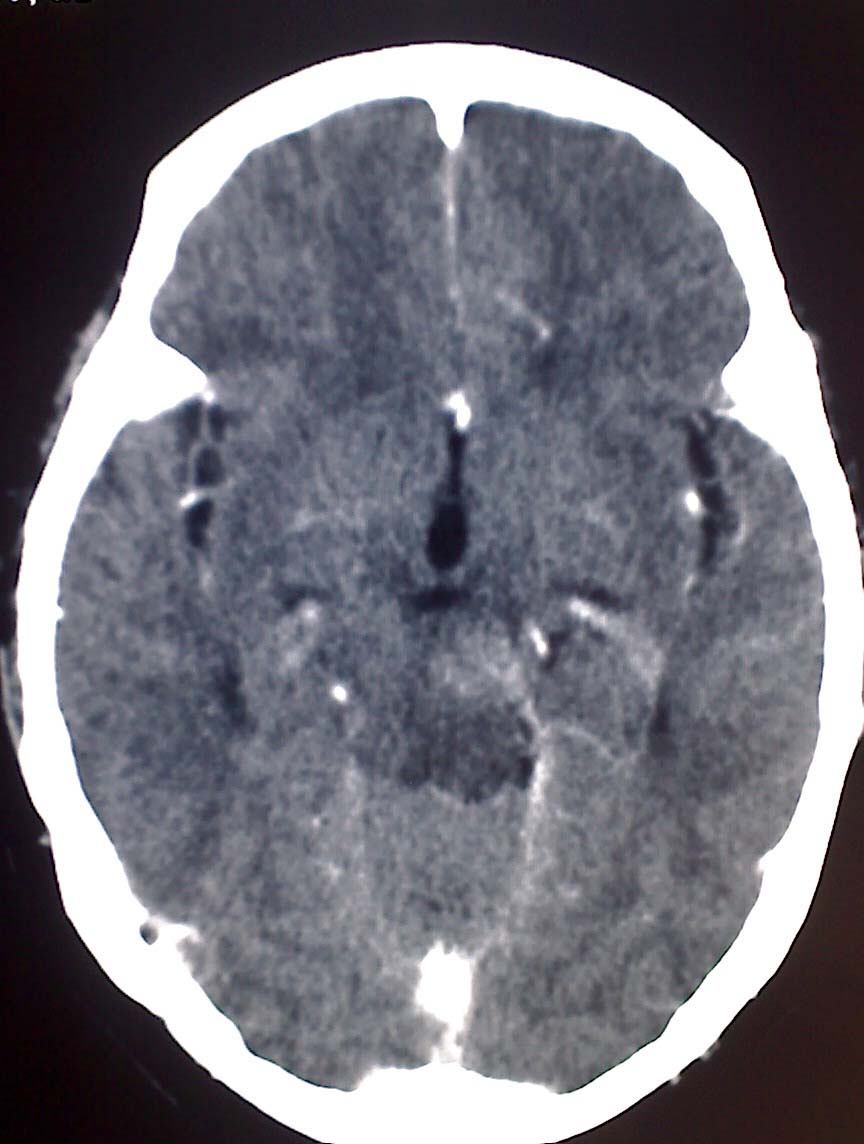

女性,56岁,查体所见,请会诊

平扫为较高密度,增强后病灶明显强化,边界清楚水肿不明显.考虑脑膜瘤.

左岩骨尖区脑膜瘤

从病变位置和强化表现看倾向脑膜瘤,但其跨越中后颅窝,也要结合临床,不能忽略三叉神经瘤,不过后者囊变较多。此病例的不足是无骨窗对照,脑膜瘤比较容易出现临近骨骼的异常。

左岩骨尖区占位病变,平扫呈高密度,病变跨中后颅窝生长,岩骨可见骨质吸收,周围未见明显水肿,增强扫描病灶明显强化。考虑左岩骨尖区脑膜瘤。

此片最大的缺憾是没骨窗,钙化及颅骨的改变不好看